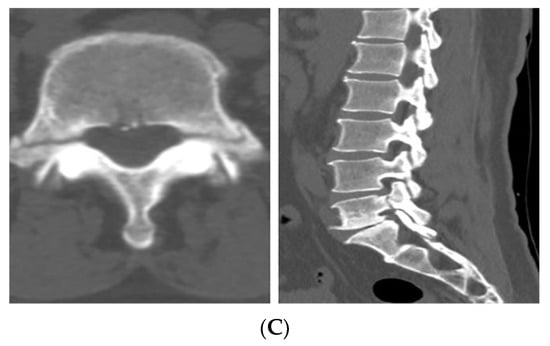

Following the decision to proceed with conservative management, the patient was prescribed acetaminophen, tramadol, and eperisone for pain control, and a thoracolumbosacral orthosis (TLSO) was applied. Light ambulation was permitted, while activities that could strain the lower lumbar regions such as twisting the torso or sitting on the floor were restricted. During the 9-day hospital stay, the patient’s LBP improved from an NRS of 7 at admission to 3, and she gradually experienced less pain during ambulation, leading to her discharge with follow-up in the outpatient clinic. 27 days after discharge, the patient visited the outpatient clinic with minimal pain and no neurological symptoms. Follow-up lumbar spine radiographs (anteroposterior, lateral, flexion, and extension views) revealed no evidence of instability or additional fracture. On the 69th day after discharge, the patient visited to the outpatient clinic pain-free and no longer required medication. CT demonstrated sclerotic changes surrounding the fracture site with partial bone bridge formation, as shown in Figure 3.

Figure 3. Follow-up CT images showing sclerotic changes around the fracture site with partial bone bridge formation, indicating progressive healing.